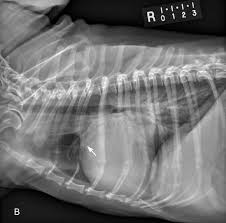

The best way to do this is to change the dog s diet. Kidney stones or kidney stone fragments can also pass through this system of tubes and into the ureter causing serious complications. However some breeds of dog are more susceptible to certain types of kidney stones than others.

Overview stones of the urinary tract begin as microscopic crystals that aggregate to form stones of variable size and shape anywhere within the urinary system including the kidneys ureters and urethra although stones of the urinary bladder are most common. Cystine stones excessive elimination of cystine in the urine is an inherited disorder of kidney tubular transport that is thought to be the primary cause of cystine stones figure 5. Follow up appointments for urinalysis and or abdominal x rays should be done every 4 6 weeks after treatment initiation to ensure stones are dissolving and new ones are not forming.

These techniques are helpful to provide the outline of the stones in your dog s kidney. Kidney stones in dogs happen when crystals or stones form in the kidneys usually due to an abnormal concentration of mineral salts in the urine. Dogs with small kidney stones really may show no signs at all.

Canine kidney stones diagnosis. Kidney stones may show up on x rays of the belly that are being taken for unrelated reasons as a so called incidental finding for instance they may be discovered when you think your pooch may have eaten something he shouldn t have like one of your favorite earrings. There are several types of bladder stones.